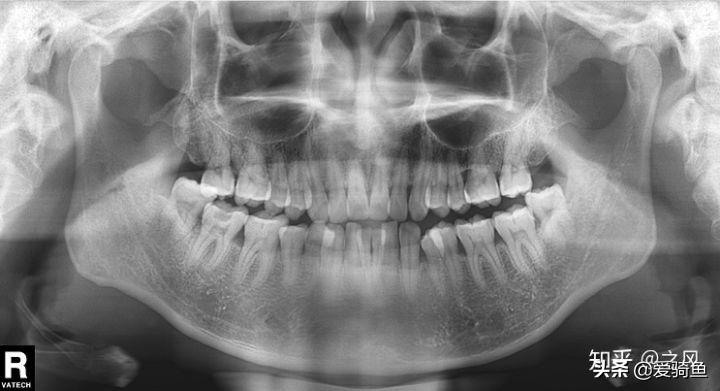

排隊等待叫號,進去后張嘴檢查下,讓去拍片子,應該就是我之前去的其他牙診所機構的口掃,這里沒有給我電子照片,下面是以前拍的。

口掃

智齒